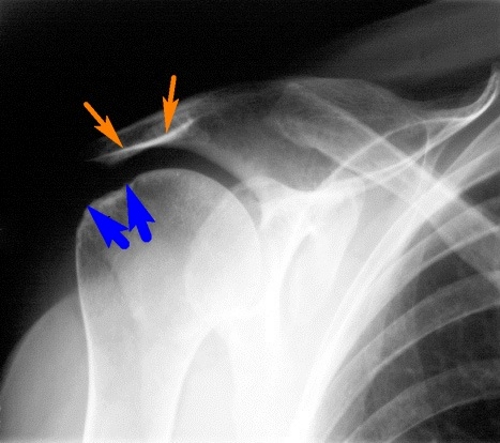

Диагностика плечевого артрита начинается с осмотра и беседы с пациентом. Это позволяет оценить степень двигательных нарушений и выявить признаки мышечной атрофии. Врач должен обратить особое внимание на хруст. Если во время обследования обнаруживается симметричное поражение, это может указывать на ревматоидный артрит. Лечение направлено на устранение причин воспаления плечевого сустава.